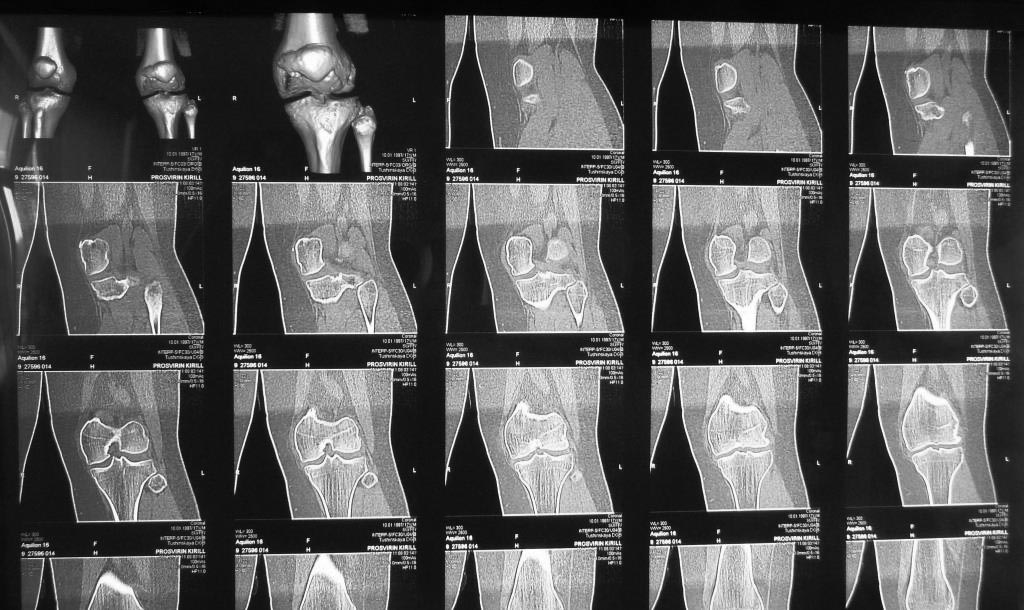

а где поперечные снимки КТ?

Виноват. Выложу позже. Технические моменты. не переписалось с диска томографа. Вы об углах?

Судя по предсавленным снимкам, у парня ретровесионная деформация шейки бедра, вальгусная деформация бедра, внутренняя ротация голени,гипотрофия наружного мыщелка бедра, возможно высокое стояние надколенника!!!